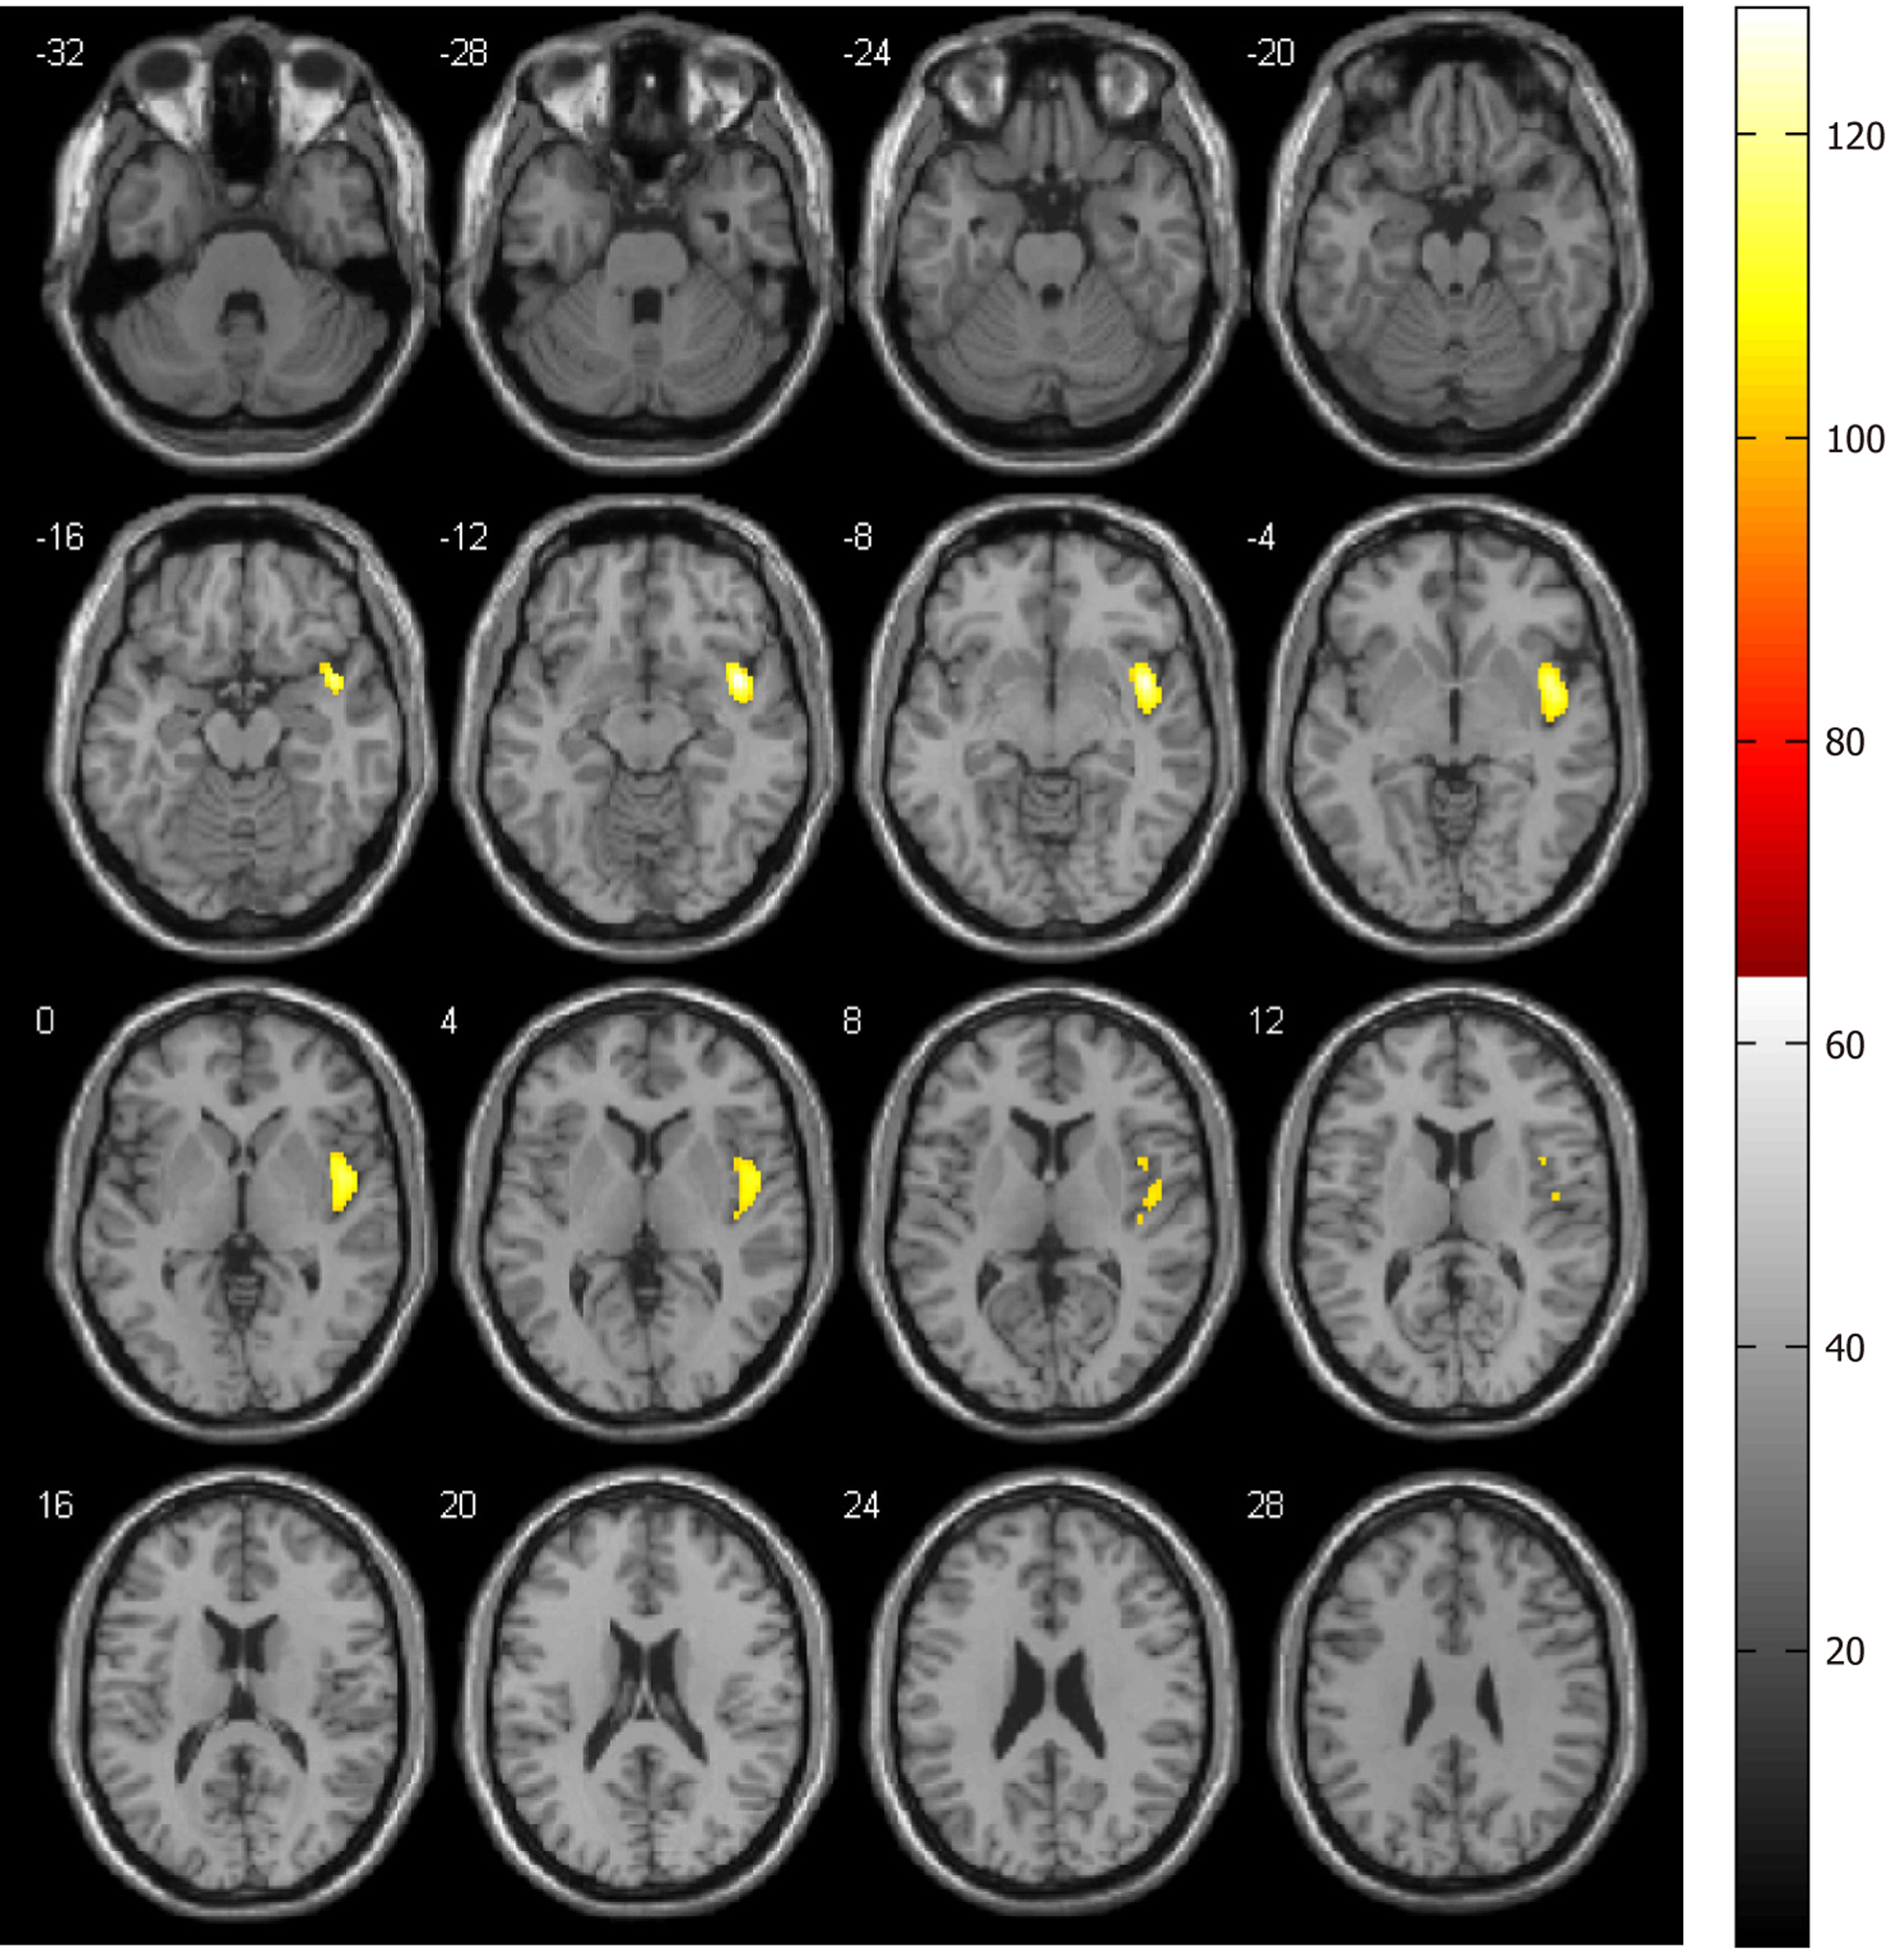

Figure 2 Voxel-wise comparison of cerebral blood flow in the right insular cortex between baseline and post-treatment with sertraline.

Significant decreases were observed in the right insula (P < 0.001, family-wise type I error rate: Corrected).